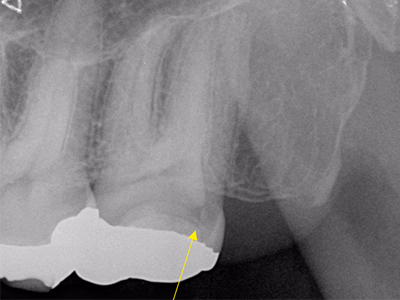

感染根管治療(リトリートメント)

右下奥歯で咬むと違和感がある/歯ぐきが腫れてきた

治療内容

- ① 顕微鏡視下根管治療(マイクロエンド)

- ② 根管拡大・洗浄2回

- ③ 2ヶ月経過観察で再生反応確認後に根管充填

- ④ マイクロスコープ下でファイバーコア築造+セラミック冠装着

約3ヶ月半(1回の治療:1~2時間)

- マイクロエンド132,000円

- ファイバーコア 22,000円

- 仮歯 6,600円

- セラミック冠 165,000円

- 術後の腫れ・痛み・出血

- 慢性根尖性歯周炎が再発する可能性

- 定期的なチェックが必要

サイナストラクトは消失し、CTでも透過像の改善を確認。

術後数日で痛み消失し、セラミック装着後も良好な咀嚼が可能。

現在は年1 回の定期チェックを継続中。